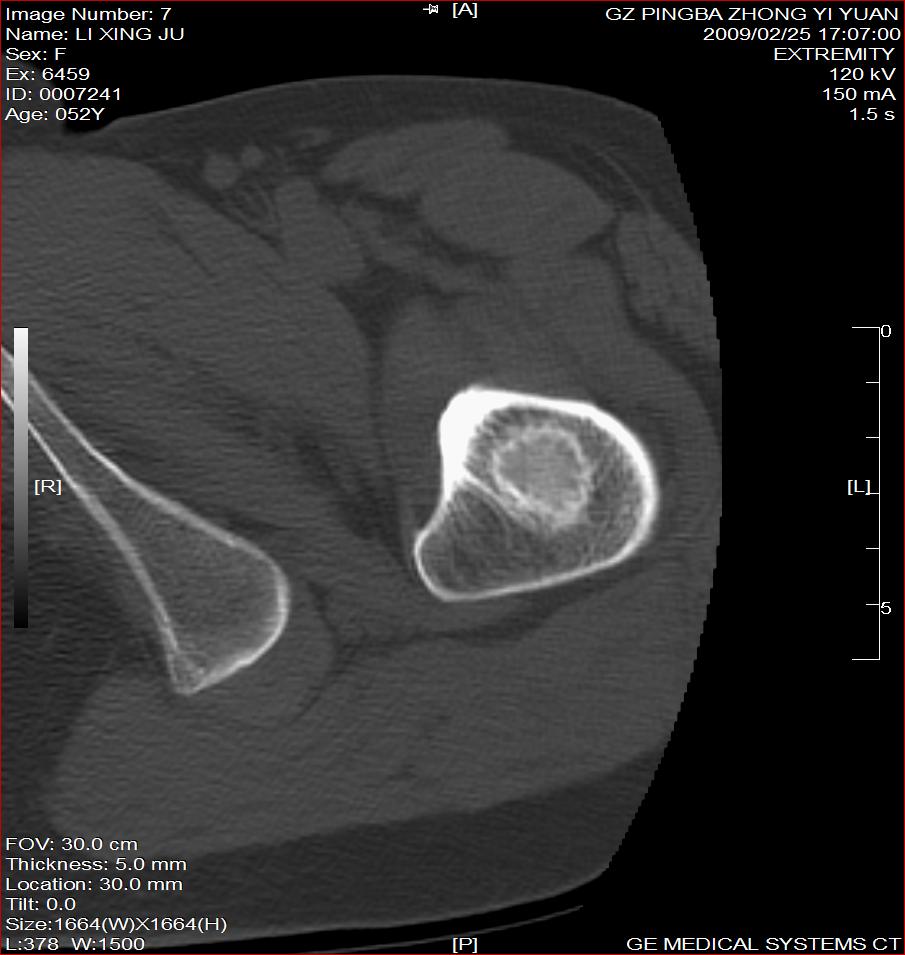

标题: CT18521:左大腿疼痛不适1+月 [打印本页]

标题: CT18521:左大腿疼痛不适1+月

考虑-----股骨骨化性纤维瘤可能性大,不除外---局限性骨纤

考虑:左股骨骨化性纤维瘤

考虑:骨纤或骨梗可能性大

考虑 左股骨骨化性纤维瘤。

骨梗塞

考虑骨化性纤维瘤可能性大